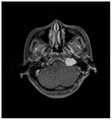

图3为听神经瘤患者的二维脑部核磁共振影像;Figure 3 is a two-dimensional brain magnetic resonance image of a patient with acoustic neuroma;

具体地,原始数据集中包含200余位病患的脑部核磁共振影像数据及其肿瘤标注结果,每位病患的数据由多张二维切片构成。在核磁共振影像数据的多种序列中,T2序列下的肿瘤区域与周遭组织的对比度更高,因此选用T2序列下的900张二维MRI图像及其标注数据作为数据集。为了便于图像的读取与处理,使用pydicom和simpleITK软件库对dicom格式的MRI图形进行处理,并将其转换为jpeg格式,得到尺寸为640*640的脑部MRI图像,如说明书附图3所示。同时将对应的标注数据用掩码图像表示,如说明书附图4所示,掩码图像的尺寸与脑部MRI图像一致。Specifically, the original data set contains brain MRI data and tumor labeling results of more than 200 patients, and each patient's data consists of multiple two-dimensional slices. Among the various sequences of MRI data, the contrast between the tumor area and the surrounding tissue under the T2 sequence is higher, so 900 two-dimensional MRI images and their annotation data under the T2 sequence were selected as the data set. In order to facilitate image reading and processing, use pydicom and simpleITK software library to process MRI graphics in dicom format and convert them into jpeg format to obtain brain MRI images with a size of 640*640, as shown in Figure 3 of the manual Show. At the same time, the corresponding labeled data is represented by a mask image, as shown in Figure 4 of the specification, the size of the mask image is consistent with that of the brain MRI image.